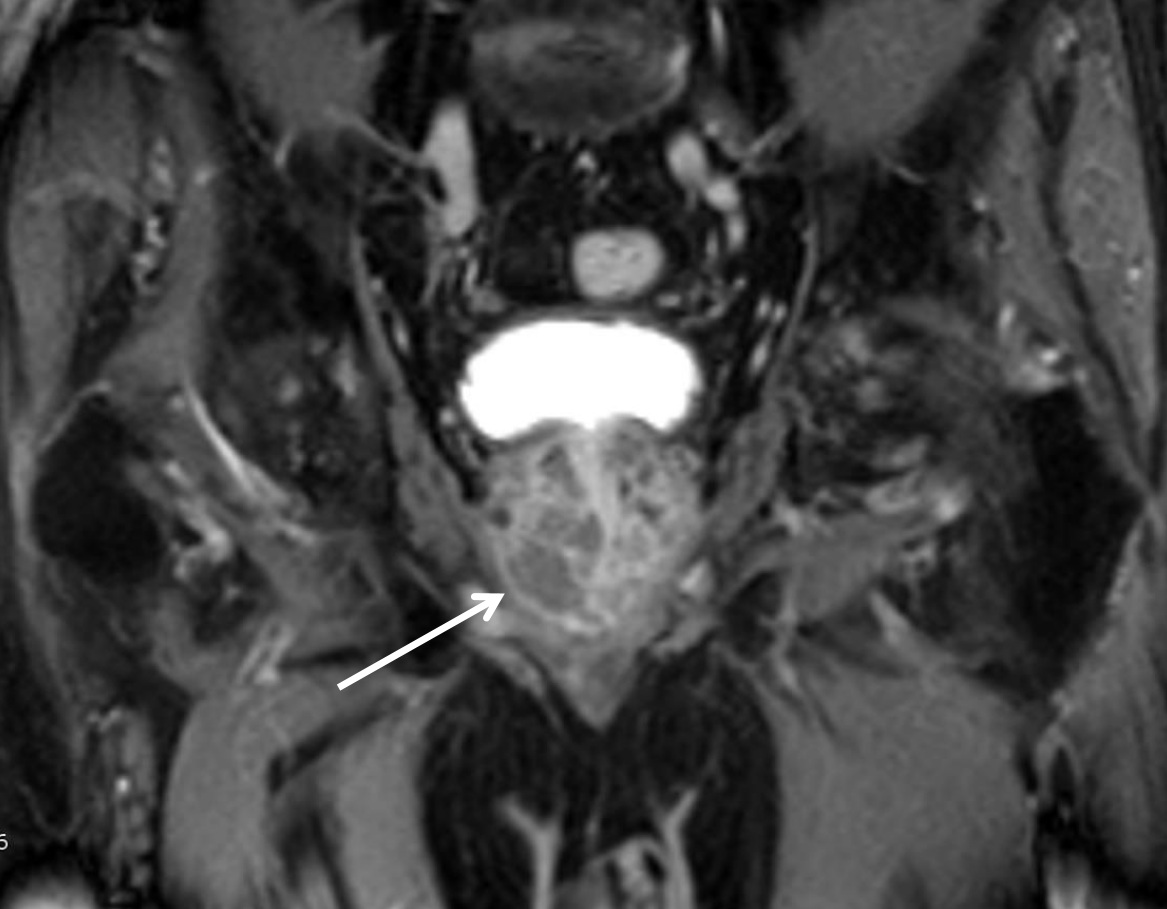

Магнитно-резонансная томография (МРТ) малого таза у женщин является важным методом диагностики различных заболеваний. На фотографиях МРТ можно увидеть органы малого таза, такие как матка, яичники, мочевой пузырь, прямая кишка и другие структуры.

Примеры фото МРТ малого таза у женщин

Ниже представлены примеры фотографий МРТ малого таза у женщин, позволяющие увидеть, как выглядят снимки и какие изменения могут быть обнаружены специалистами.